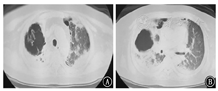

患者男,64岁,因"反复咳嗽、咳痰、喘憋18年,加重20余天"于2018年1月26日入院。患者近18年反复出现咳嗽、咳痰、喘憋,诊断为COPD、肺气肿、肺大疱、矽肺Ⅰ期等。近3年因COPD急性加重多次住院,经抗感染、化痰、平喘等治疗可好转,院外长期吸入沙美特罗替卡松粉(舒利迭)、噻托溴铵粉(思力华),口服止咳、化痰药物。2018年1月3日患者受凉后再次出现咳嗽、咳痰、喘憋加重,就诊于北京某医院。2018年1月3日胸部CT示两肺见多发粗大索条影,边缘模糊,肺气肿,多发肺大疱,左肺下叶球形肺不张,双侧胸膜肥厚,右侧胸膜钙化,右肺下叶支气管扩张(图1),考虑肺部感染。住院后给予哌拉西林舒巴坦钠、比阿培南、莫西沙星等抗感染,并给予甲泼尼龙抗炎(具体不详)。患者病情好转,于2018年1月24日出院。出院后按医嘱继续口服醋酸泼尼松40 mg/d。2018年1月26日患者出现发热,体温最高达38 ℃,咳嗽、咳痰、憋喘较前加重,安静状态憋喘,咳痰带鲜红血丝,伴纳差、乏力,无盗汗,无胸痛,无头晕、恶心,来北京老年医院急诊就诊。血常规:白细胞计数23.69×109/L,红细胞计数5.42×1012/L,血红蛋白158 g/L,血小板计数173×109/L,中性粒细胞比例87.3%,淋巴细胞比例5.7%;血气分析:pH值7.45,PaCO2为41.4 mmHg(1 mmHg=0.133 kPa),PaO2为72.2 mmHg,SaO2为94.5%;血凝指标、D-二聚体、肌钙蛋白I、肌酸激酶同功酶、B型钠酸肽均正常。2018年1月26日胸部CT与2018年1月3日比较,双肺新出现散在斑片影及斑点影,伴大小不等空洞,部分空洞周围可见晕征(图2),考虑双肺感染进展,收住北京老年医院呼吸康复科。

患者短期内双肺出现散在斑片影及斑点影,伴大小不等空洞,考虑肺部感染性疾病。入院后给予比阿培南(0.6 g,静脉滴注,2次/d)+万古霉素(0.5 g,静脉滴注,每8小时1次)联合抗细菌,继续醋酸泼尼松40 mg/d口服抗炎,并给予多索茶碱静脉滴注、雾化吸入布地奈德及特布他林平喘,氨溴索静脉滴注化痰,皮下注射胰岛素控制血糖等治疗。完善相关检查,ESR为47 mm/h;C反应蛋白96.10 mg/L;生化:钾4.0 mmol/L,钠131.0 mmol/L,氯96.0 mmol/L,空腹血糖17.0 mmol/L,尿素7.1 mmol/L,肌酐68.0 μmol/L,丙氨酸氨基转移酶29.0 U/L,天门冬氨酸氨基转移酶13.0 U/L,乳酸脱氢酶253 U/L,肌酸激酶79 U/L,总蛋白51.1 g/L,白蛋白30.8 g/L。尿常规:葡萄糖++++;血结核菌38kD蛋白阴性,结核菌外膜抗体阳性;结核菌素试验阴性;降钙素原、抗链球菌O、类风湿因子、自身抗体系列、肿瘤相关抗原系列、粪常规均正常。术前四项(乙肝表面抗原、丙肝抗体、人类免疫缺陷病毒抗体、梅毒血清特异性抗体)阴性。心电图大致正常。心脏超声:主动脉瓣钙化,左室后壁运动幅度稍减低,左室舒张功能减低。腹部超声:脂肪肝,余未见异常。肺功能:第1秒用力呼气容积/FVC为43.22%,第1秒用力呼气容积占预计值百分比为24.9%,提示阻塞性通气功能障碍,小气道功能障碍,残气量/肺总量轻度增高,弥散功能重度减低。痰涂片找抗酸杆菌阴性(3次)。患者入院当日(2018年1月26日)发热,最高体温达38 ℃;1月27日体温正常;1月28日再次发热,最高体温达38.1 ℃;1月29日之后未再发热,憋喘较前略好转,痰中带血减少。1月29日痰涂片:革兰阳性球菌可见;痰真菌培养:白色假丝酵母菌+。1月30日血1,3-β-D葡聚糖检测(G试验):247.3 μg/L(升高);血常规:白细胞计数12.56×109/L,红细胞计数5.00×1012/L,血红蛋白143 g/L,血小板计数179×109/L,中性粒细胞比例85.3%,淋巴细胞比例7.6%;C反应蛋白55.10 mg/L;血气分析:pH值7.43,PaCO2为48.4 mmHg,PaO2为81.6 mmHg,SaO2为95.8%。入院后每日皮下注射胰岛素累积剂量56 IU。1月26日至1月30日血糖控制不理想,空腹血糖波动于11~18 mmol/L,早餐及午餐后2 h血糖波动于10~18 mmol/L,晚餐后2 h血糖波动于15~21 mmol/L。患者痰检见白色假丝酵母菌+,G试验轻度增高(近期有应用哌拉西林舒巴坦钠史,不排除干扰),近期有糖皮质激素应用史,血糖控制欠佳,综合以上因素,考虑肺真菌感染不排除。1月30日给予伏立康唑200 mg口服抗真菌,每12小时1次(第1个24小时400 mg/次),同时减量醋酸泼尼松为30 mg/d。2月2日痰真菌培养:曲霉菌属+(2次),白色假丝酵母菌+,进一步支持真菌感染,建议行气管镜检查,患者因喘憋不适,一直不同意。之后又有2次痰培养:曲霉菌属1~2个菌落。2月5日患者憋喘较重,复查血常规:白细胞计数23.32×109/L,红细胞计数5.22×1012/L,血红蛋白151 g/L,血小板计数208×109/L,中性粒细胞比例92.2%,淋巴细胞比例3.7%;C反应蛋白229.80 mg/L;血气分析:pH值7.44,PaCO2为47.3 mmHg,PaO2为82.3 mmHg,SaO2为95.7%,提示感染加重。2月5日伏立康唑改为0.3 g,静脉滴注,每12小时1次。2月6日胸部CT示双肺散在斑片影及斑点影,伴大小不等空洞,与1月26日胸部CT比较右肺上叶空洞增大,右肺上叶病变进展(图3)。继续伏立康唑静脉滴注抗真菌,比阿培南联合万古霉素抗细菌治疗。2月12日胸部CT示右肺上叶空洞较2月6日进一步增大(图4)。2月12日血气分析:pH值7.45,PaCO2为57.2 mmHg,PaO2为78.3 mmHg,SaO2为95.1%。经反复动员,2月13日患者同意气管镜检查,结果(图5)示主气管黏膜表面可见白色分泌物附着;左上叶支气管黏膜充血明显,可见大量脓性分泌物;右上叶支气管各叶段开口变窄,以右上叶尖段开口变窄明显;右上叶支气管黏膜充血水肿明显,活检或刷检易出血。气管镜刷片及灌洗液病理见少许坏死物及中性粒细胞,未见肿瘤细胞。支气管镜肺活检(右上叶)病理:送检肺组织慢性炎,肺间质可见单核细胞浸润,纤维组织增生,肺泡上皮增生,肺组织表面附着成团的坏死物,坏死物中可见真菌菌丝及孢子。气管镜刷片培养:曲霉菌属1个菌落;气管镜后痰培养:曲霉菌属4个菌落。患者IPA诊断依据充足,应用伏立康唑效果差,2月14日改为两性霉素B脂质体静脉滴注,从10 mg/d始,逐日递增,增至150 mg/d时患者精神萎靡、憋喘、乏力、纳差、尿少、肾功能异常,尿素18.5 mmol/L,肌酐166 μmol/L,总蛋白45.6 g/L,白蛋白26.9 g/L。2月18日血气分析:pH值7.38,PaCO2为55.4 mmHg,PaO2为72.4 mmHg,SaO2为93.5%。考虑患者对该药不良反应较大,停用两性霉素B脂质体。2月19日给予伏立康唑(0.3 g,静脉滴注,每12小时1次)联合卡泊芬净(50 mg/d,静脉滴注)抗曲霉菌治疗。2月20日后患者多次血气分析示PaCO2升高,波动于56~79 mmHg,PaO2低,波动于50~80 mmHg,给予保肾、人血白蛋白支持、无创呼吸机辅助通气等治疗。口服泼尼松经逐渐减量,于2月17日后停用。住院期间患者一直纳差,进食量少,尽管每日皮下注射胰岛素累积剂量60 IU,但血糖仍控制不理想,空腹血糖波动于12~20 mmol/L,餐后2 h血糖波动于14~26 mmol/L;自停用泼尼松后,血糖逐渐好转,空腹血糖波动于8~10 mmol/L,餐后2 h血糖波动于11~14 mmol/L。3月6日血气分析:pH值7.35,PaCO2为55.4 mmHg,PaO2为72.4 mmHg,SaO2为93.5%。3月6日胸部CT示双肺多发空洞,右肺上叶空洞较前增大,双肺病变继续进展(图6)。治疗效果不理想,家属要求转院。